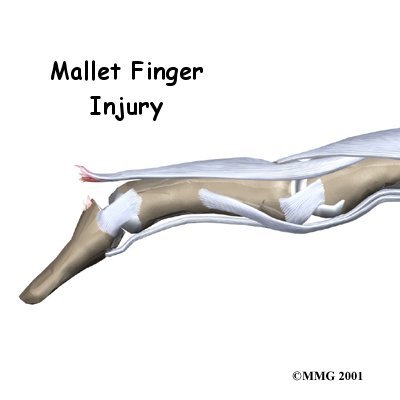

Mallet Finger Injuries

When you think about how much we use our hands, it's not hard to understand why injuries to the fingers are common. Most of these injuries heal without significant problems. One such injury is an injury to the distal interphalangeal, or DIP, joint of the finger. This joint is commonly injured during sporting activities such as baseball. If the tip of the finger is struck with the ball, the tendon that attaches to the small bone underneath can be injured. Untreated, this can cause the end of the ...